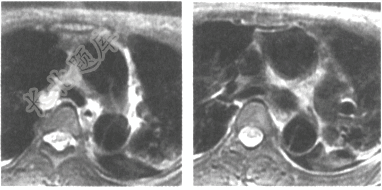

- 单项选择题女,胸骨后疼痛3小时就诊,MRI检查如下图,应诊断是

A、主动脉夹层(DeBakeyⅠ型)

B、主动脉血栓

C、主动脉夹层(DeBakeyⅢ型)

D、主动脉瘤

E、主动脉夹层(DeBakeyⅡ型)